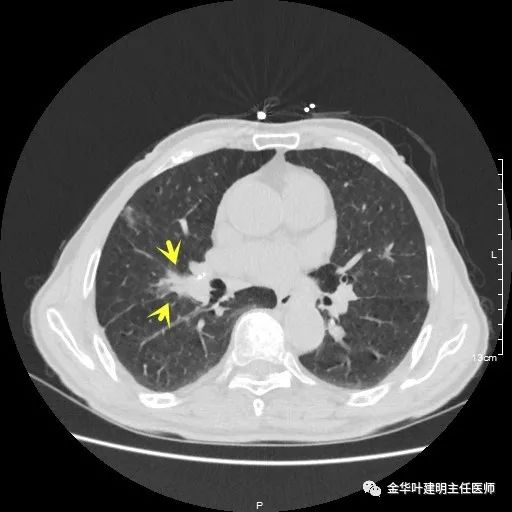

以上示右下叶病灶5。也是主病灶,是实性块状分叶的占位性病变,基本可以肯定是肺癌。单病灶看需下叶切除并清扫淋巴结。

以上示右下叶病灶6。同样是囊腔型病灶,但较前几个范围小,可囊壁同样为磨玻璃影,也是较为典型的囊腔型肺癌表现,单灶来看可下叶背段切除。